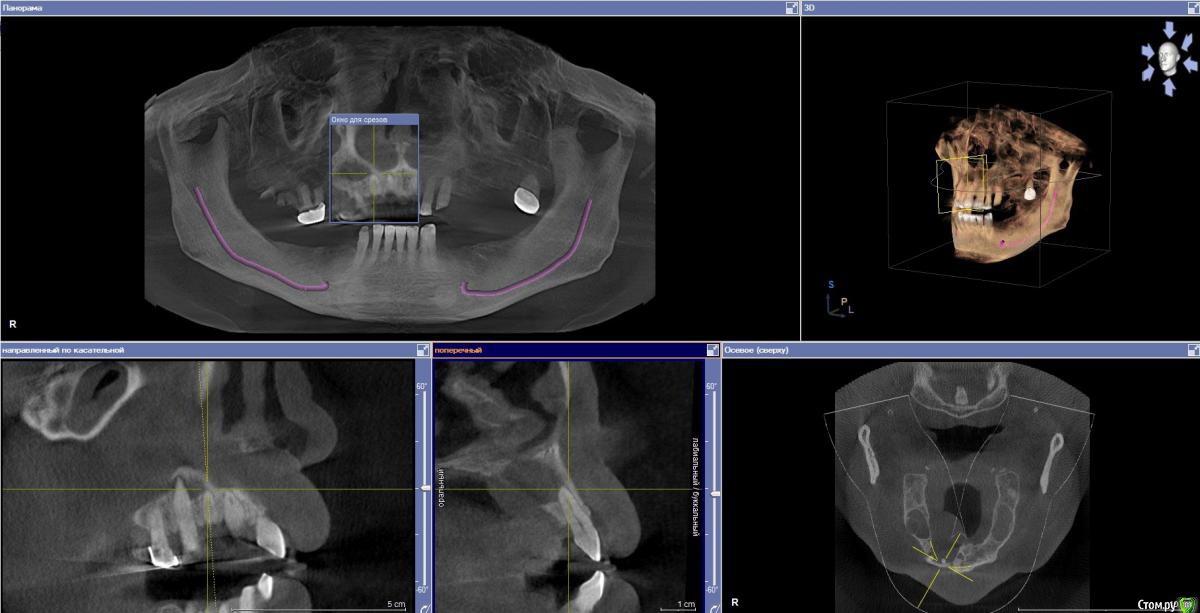

Doctormet Опубликовано 30 октября, 2015 Поделиться Опубликовано 30 октября, 2015 Доктора, приветствую! Нужна помощь в одном клиническом случае!Пациент обратился с целью протезирования. Жалоб на день осмотра не было. Замечал увеличивающееся образование в области неба в течение года. Осмотр: отмечается стираемость зубов передней группы на н\ч и в\ч примерно на 1 мм. Зубы 1.1, 1.2, 1.3 интактные, перкуссия безболезненная. В области твердого неба справа плотное безболезненное образование.Рентгенограмма: Разрежение включает верхушки корней 1.2, 1.3, 1.1, отсутствует латеральная стенка резцового канала, дно полости носа от 1.1 до 1.3 и небная стенка альвеолярного отростка от 1.1 до 1.5. Отмечается двустороннее затемнение верхнечелюстных пазух.Пациент заядлый курильщик. Травм в анамнезе не отмечает.В планах сдача анализов на гепатит, ВИЧ, сифилис, исключение сахарного диабета.Что можно предположить в данном случае? Связано ли данное образование с перегрузкой передних зубов, ЛОР патологией, либо же это киста носонебного канала или опухолевое образование?Снимки прилагаю. Спасибо! Ссылка на комментарий